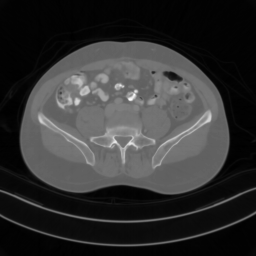

![]() |

| PSNR = dB | PSNR = 15.58 dB | PSNR = 34.28 dB | PSNR = 34.67 dB | PSNR = 35.83 dB |

Main results: In Table 1, we present quantitative results and in Figure 2, we show visualizations in the axial, coronal, and sagittal planes. Our methods consistently outperform the second-best baseline across most views, achieving nearly 1 dB higher PSNR on average. Despite incorporating a few additional input updates to enforce data consistency, our method reaches competitive performance with only 30 sampling steps. Based on the visualizations, we observe that DDS introduces slight artifacts along the horizontal direction, particularly noticeable in the coronal and sagittal views. In contrast, our method produces cleaner reconstructions with fewer artifacts in these orientations.